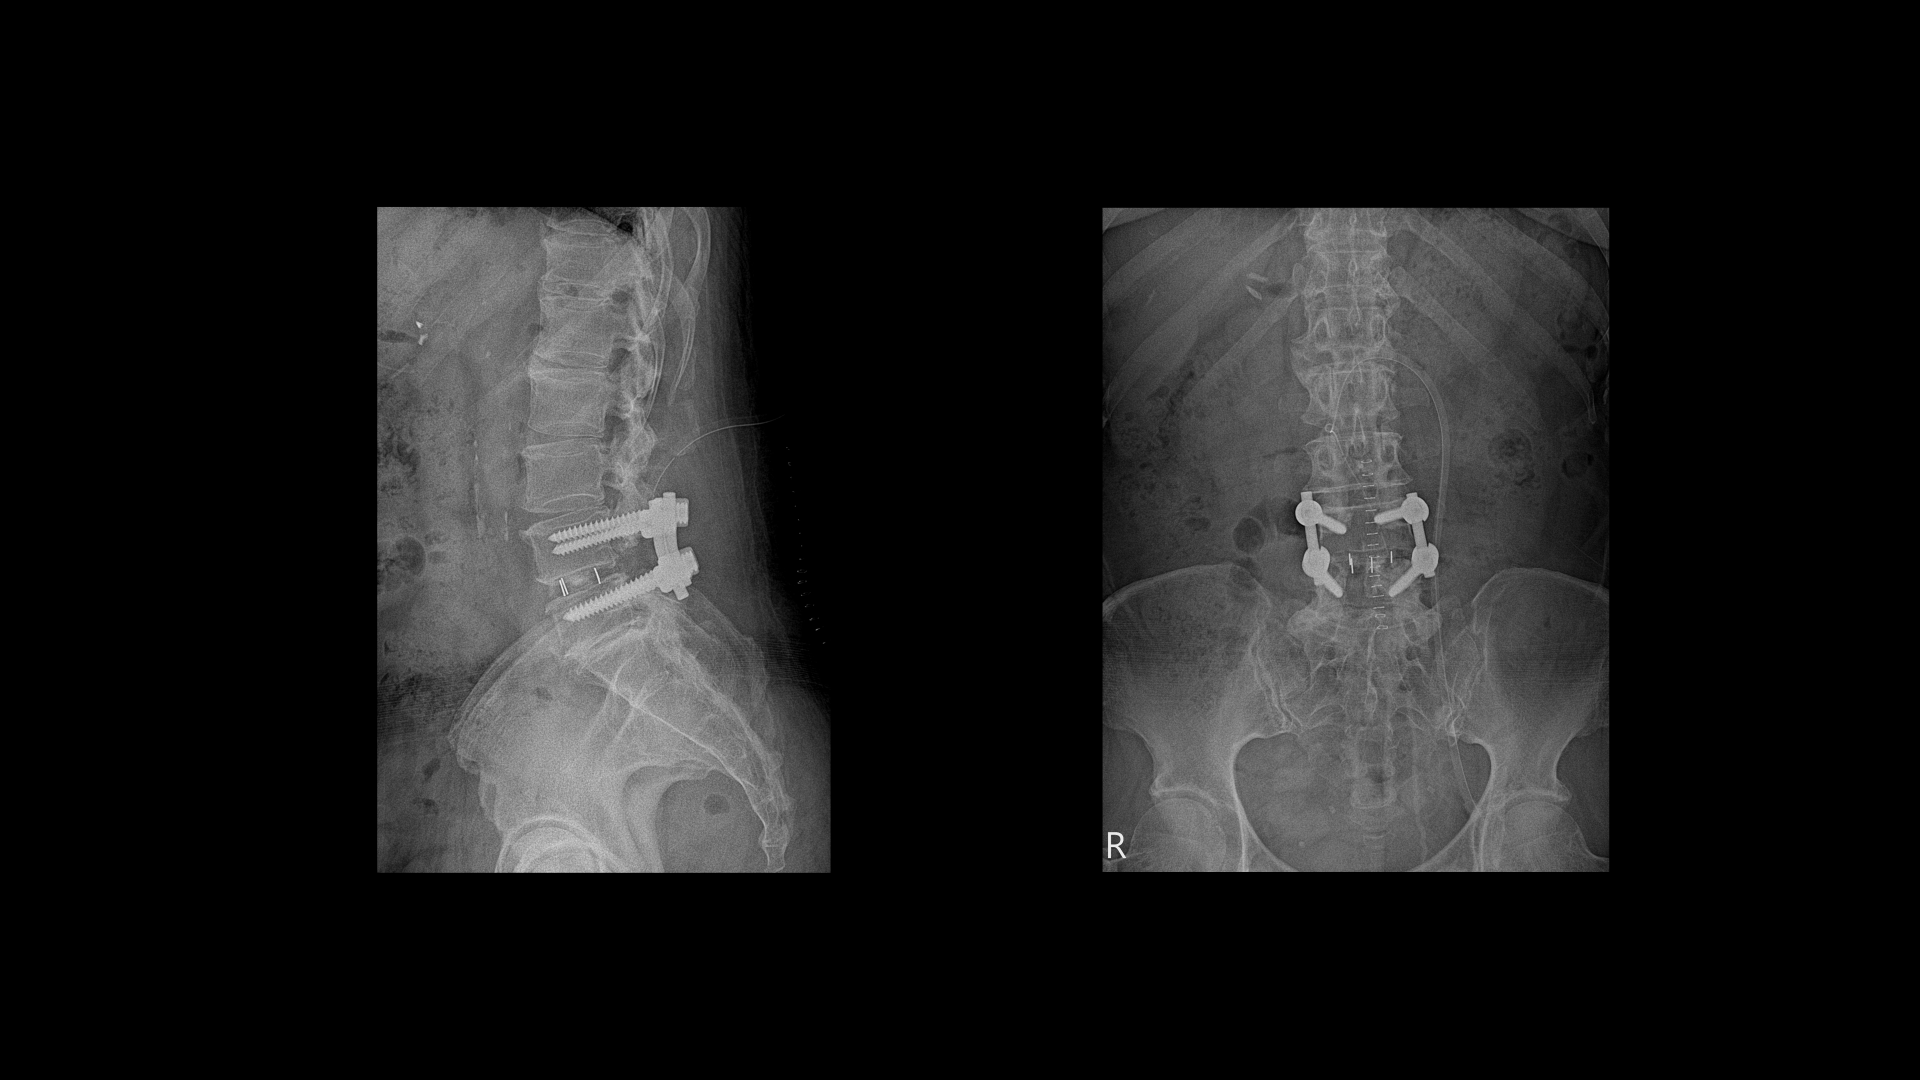

5번 1번을 보면 후궁에 수술한 자국이 보입니다.

4번 5번에도 후궁 쪽 양쪽으로 수술한 자국이 보입니다.

올해 초에 디스크가 4번 5번에서 또 오른쪽으로 심하게 터져서 결국은 후궁과 후관절, 황색인대를 모두 다 제거하고 나사를 박는 유합술을 하셨습니다.